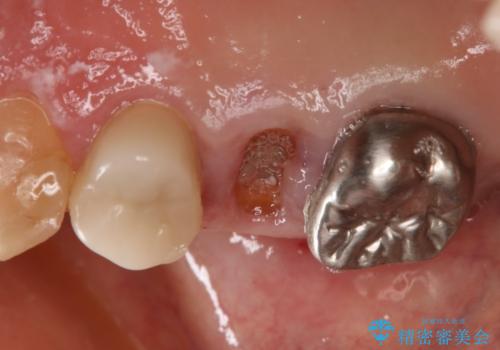

残根状態で保存不可能と判断し、抜歯した上で補綴することを提案しました。

インプラント治療を希望されたので治療の期間・回数の少ない抜歯即時埋入インプラントでの治療を計画しました。

抜歯と同時にインプラントを埋入することで治療の期間・回数を減らし、患者様への負担を大幅に軽減することができます。